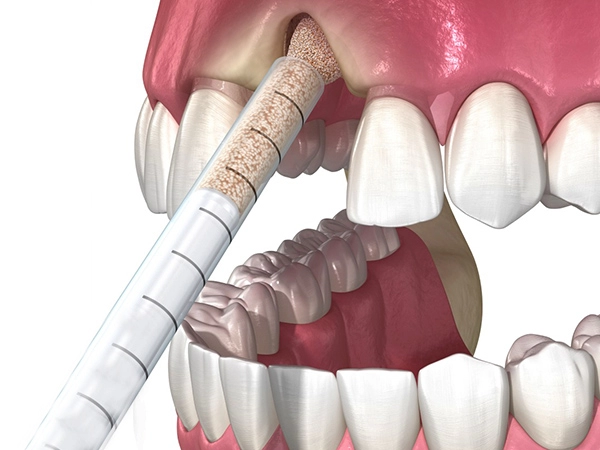

Проводится и для верхней, и для нижней челюсти. Суть метода в ведении специального костного материала, который провоцирует регенерацию собственной кости. Их (материалов) существует несколько видов: аутогенные, аллогенные, ксеногенные — и доктор подбирает, подходящий индивидуально именно вашему организму.

Проводится и для верхней, и для нижней челюсти. Суть метода в ведении специального костного материала, который провоцирует регенерацию собственной кости. Их (материалов) существует несколько видов: аутогенные, аллогенные, ксеногенные — и доктор подбирает, подходящий индивидуально именно вашему организму.